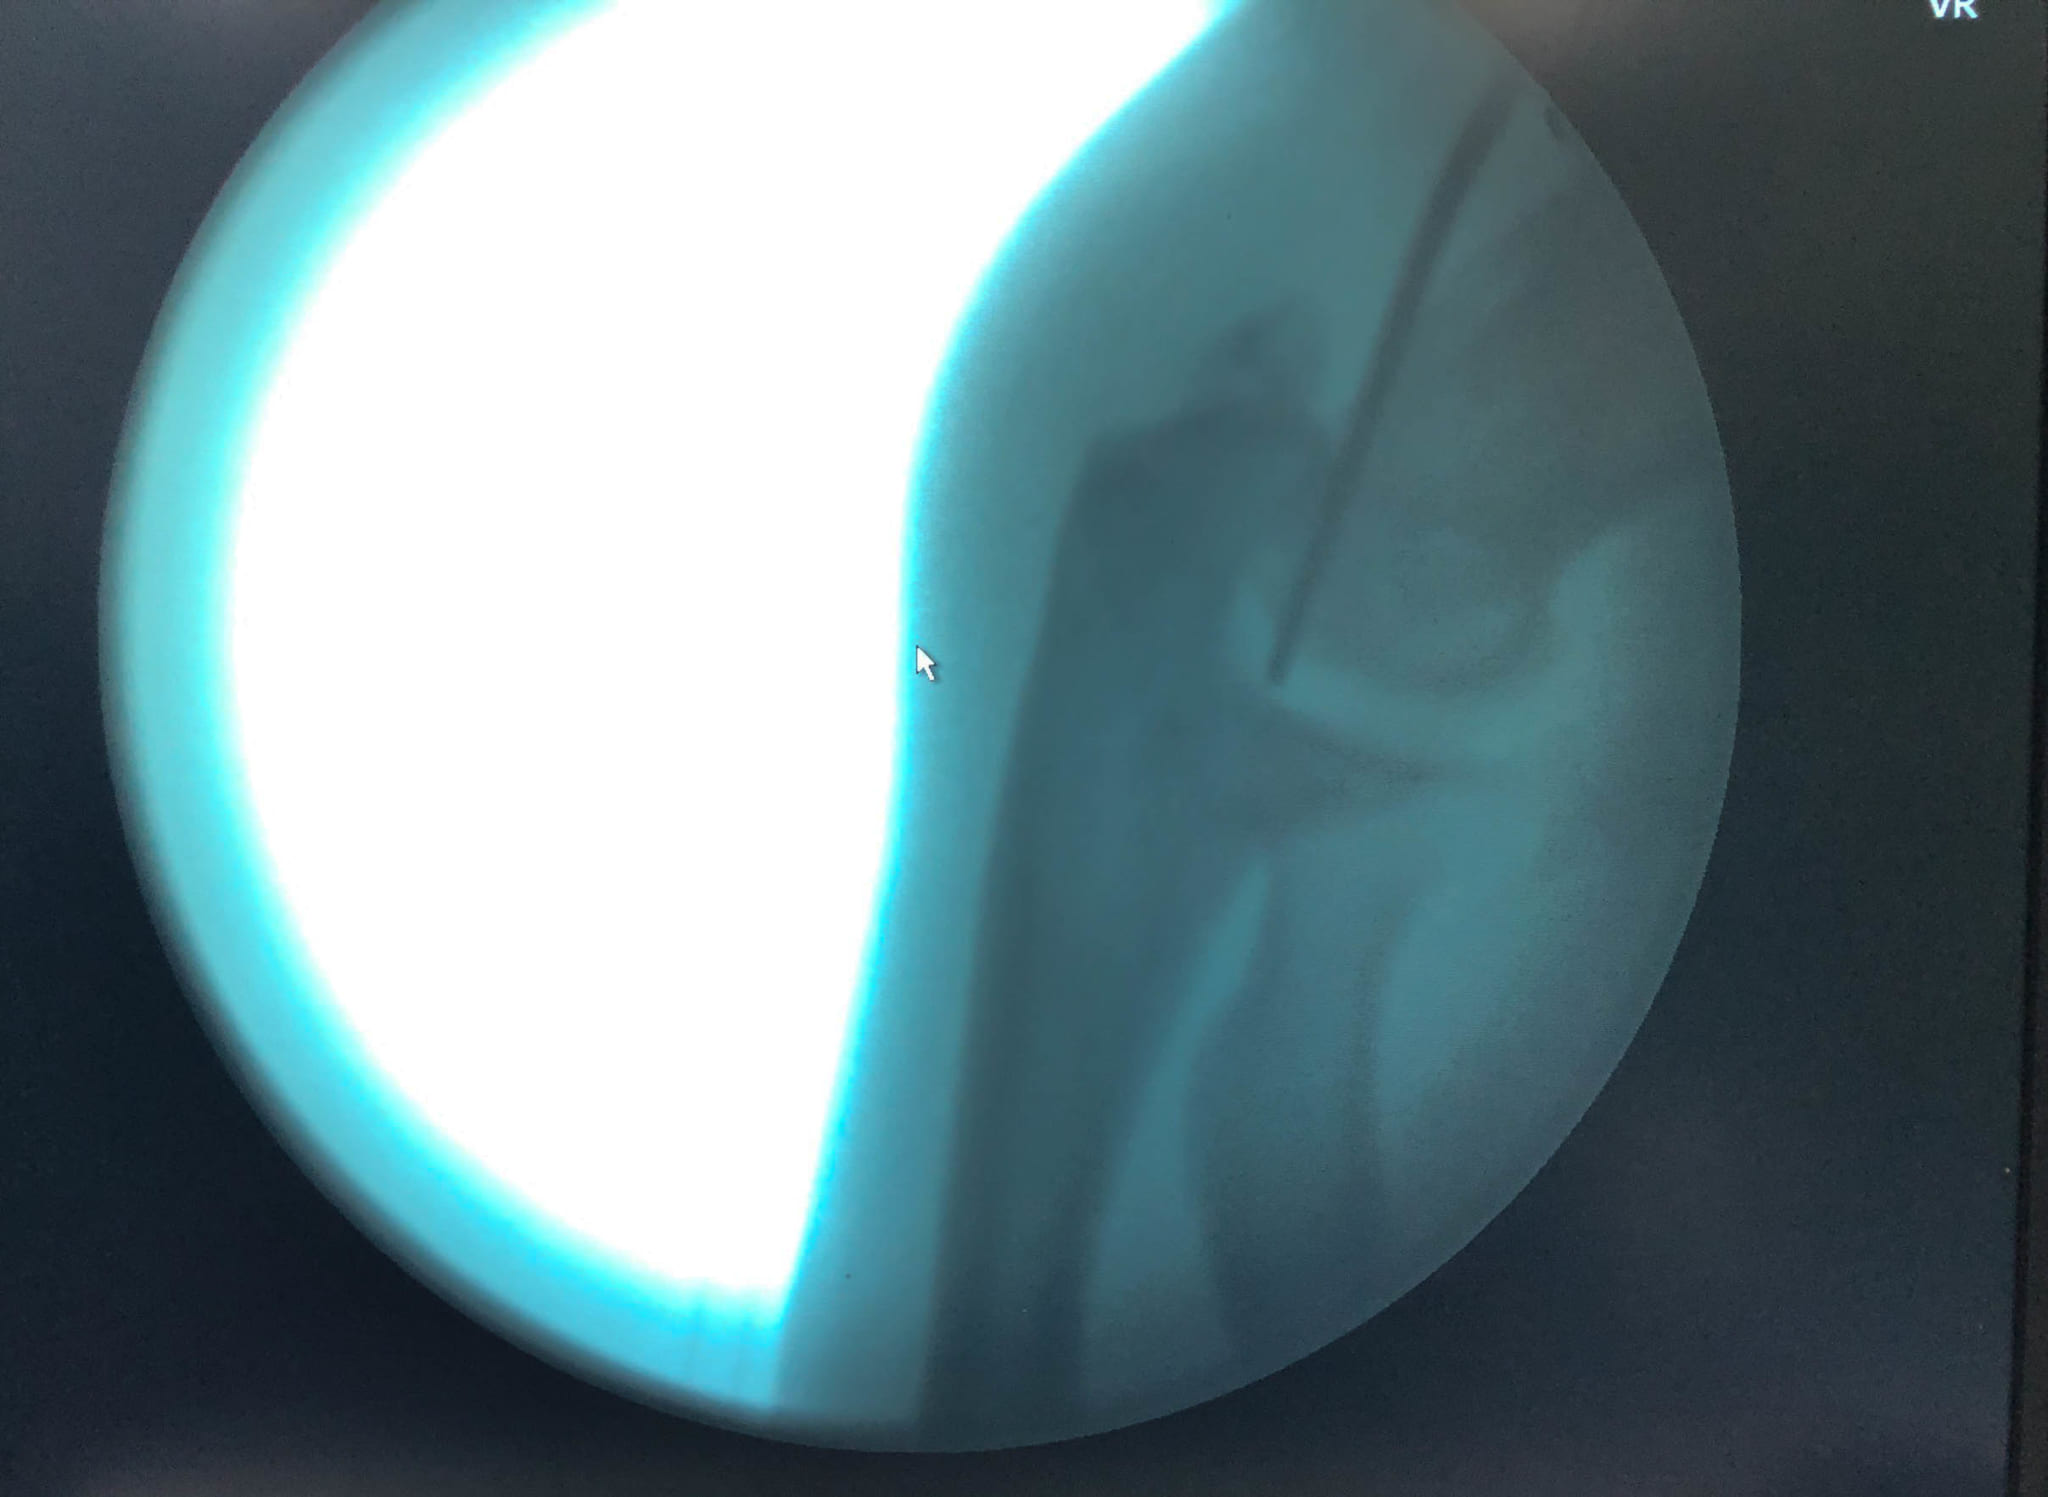

- Ca phẫu thuật được thực hiện thành công

- Hình ảnh sau mổ của bệnh nhân